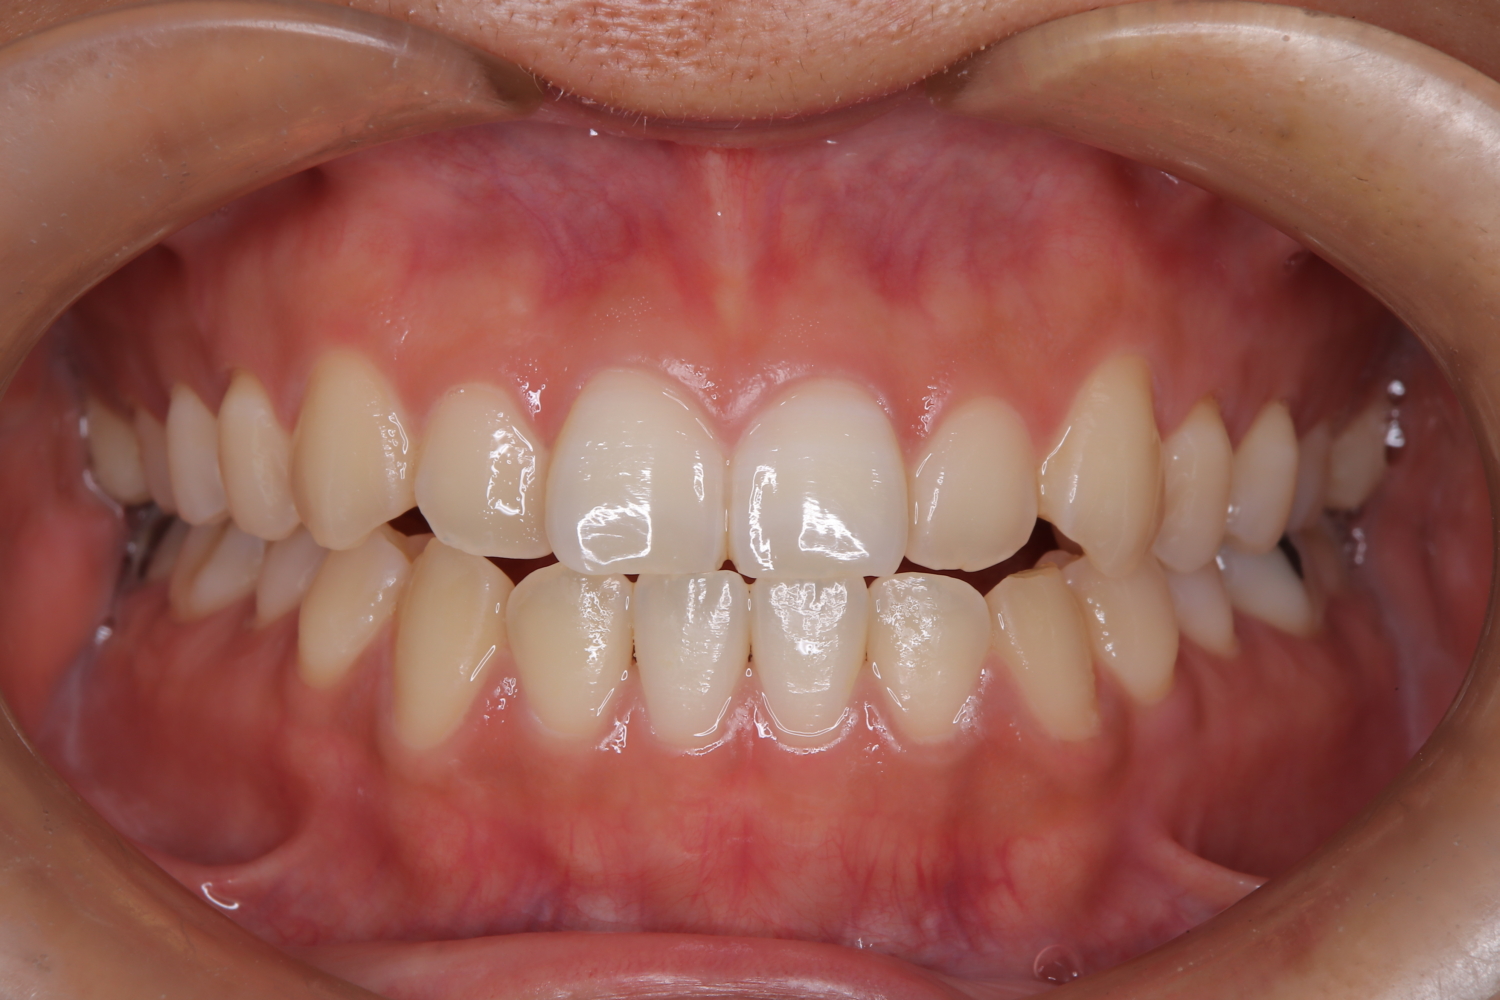

受け口の改善を主訴にご来院された患者様です。

軽度の下顎前突と診断し、マウスピース矯正装置(インビザライン)を用いて治療を行うこととしました。

治療の際はゴム掛けが必要になりましたが、患者様が非常に真面目に使用してくださったおかげで、スムーズに治療が進みました。途中の海外赴任という大きな予定変更がありましたが、そのご努力の甲斐あって、無事に渡航前に矯正を完了することができました。